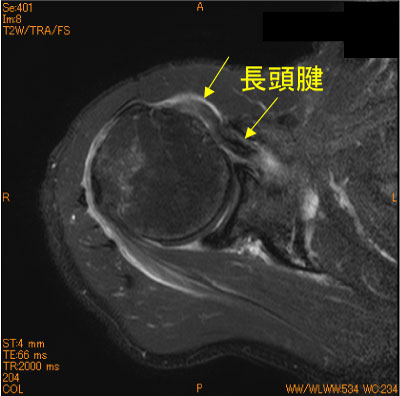

長頭腱脱臼-肩関節MRI-

70代男性、転倒後疼痛肩。

棘上筋腱、棘下筋腱の全層広範断裂に目を奪われ、長頭腱の脱臼を見逃してはならない。

必ず長頭腱の走行をcheckすること。

![]() Axial T2WI 脂肪抑制 |